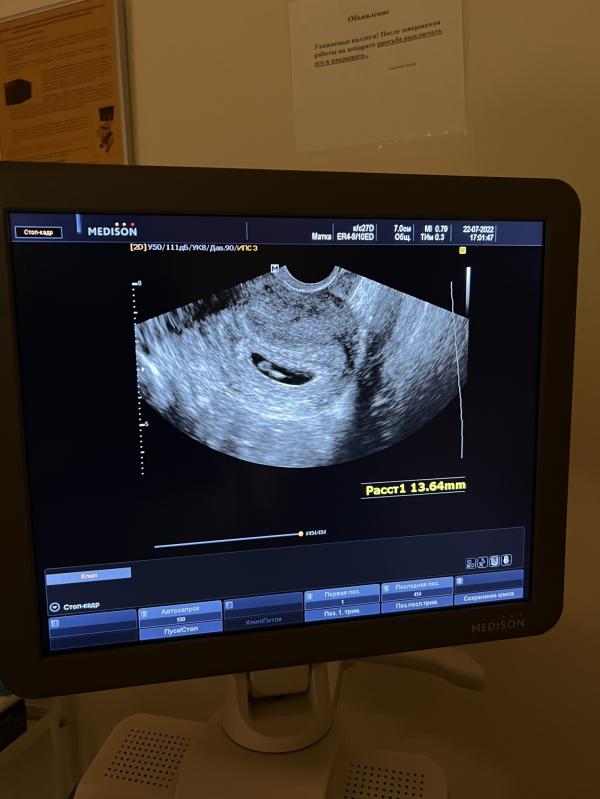

Сегодня ходили с мужем на узи, делали ещё вагинально. Наконец то увидели малыша 🥳

По узи 6 недель, малыш 11 мм. Сказали что все отлично и все хорошо развивается. Я на кушетке чуть не заплакала когда его увидела 🥹